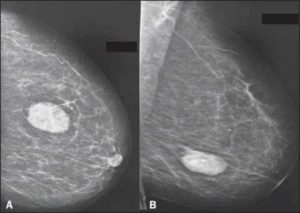

Как выглядит фиброаденома (нажмите для увеличения)

- Периканикулярная. В случае такой опухоли разрастание соединительной ткани происходит в приделах одной дольки железы. Опухоль чётко ограничена от окружающий тканей, плотная, расположена рядом с выводными канальцами молочной железы, но не прорастает в них. Опухоль может пропитываться солями кальция (чаще это происходит у пожилых женщин), и образовывать кальцинаты, которые хорошо видны на маммограмме.